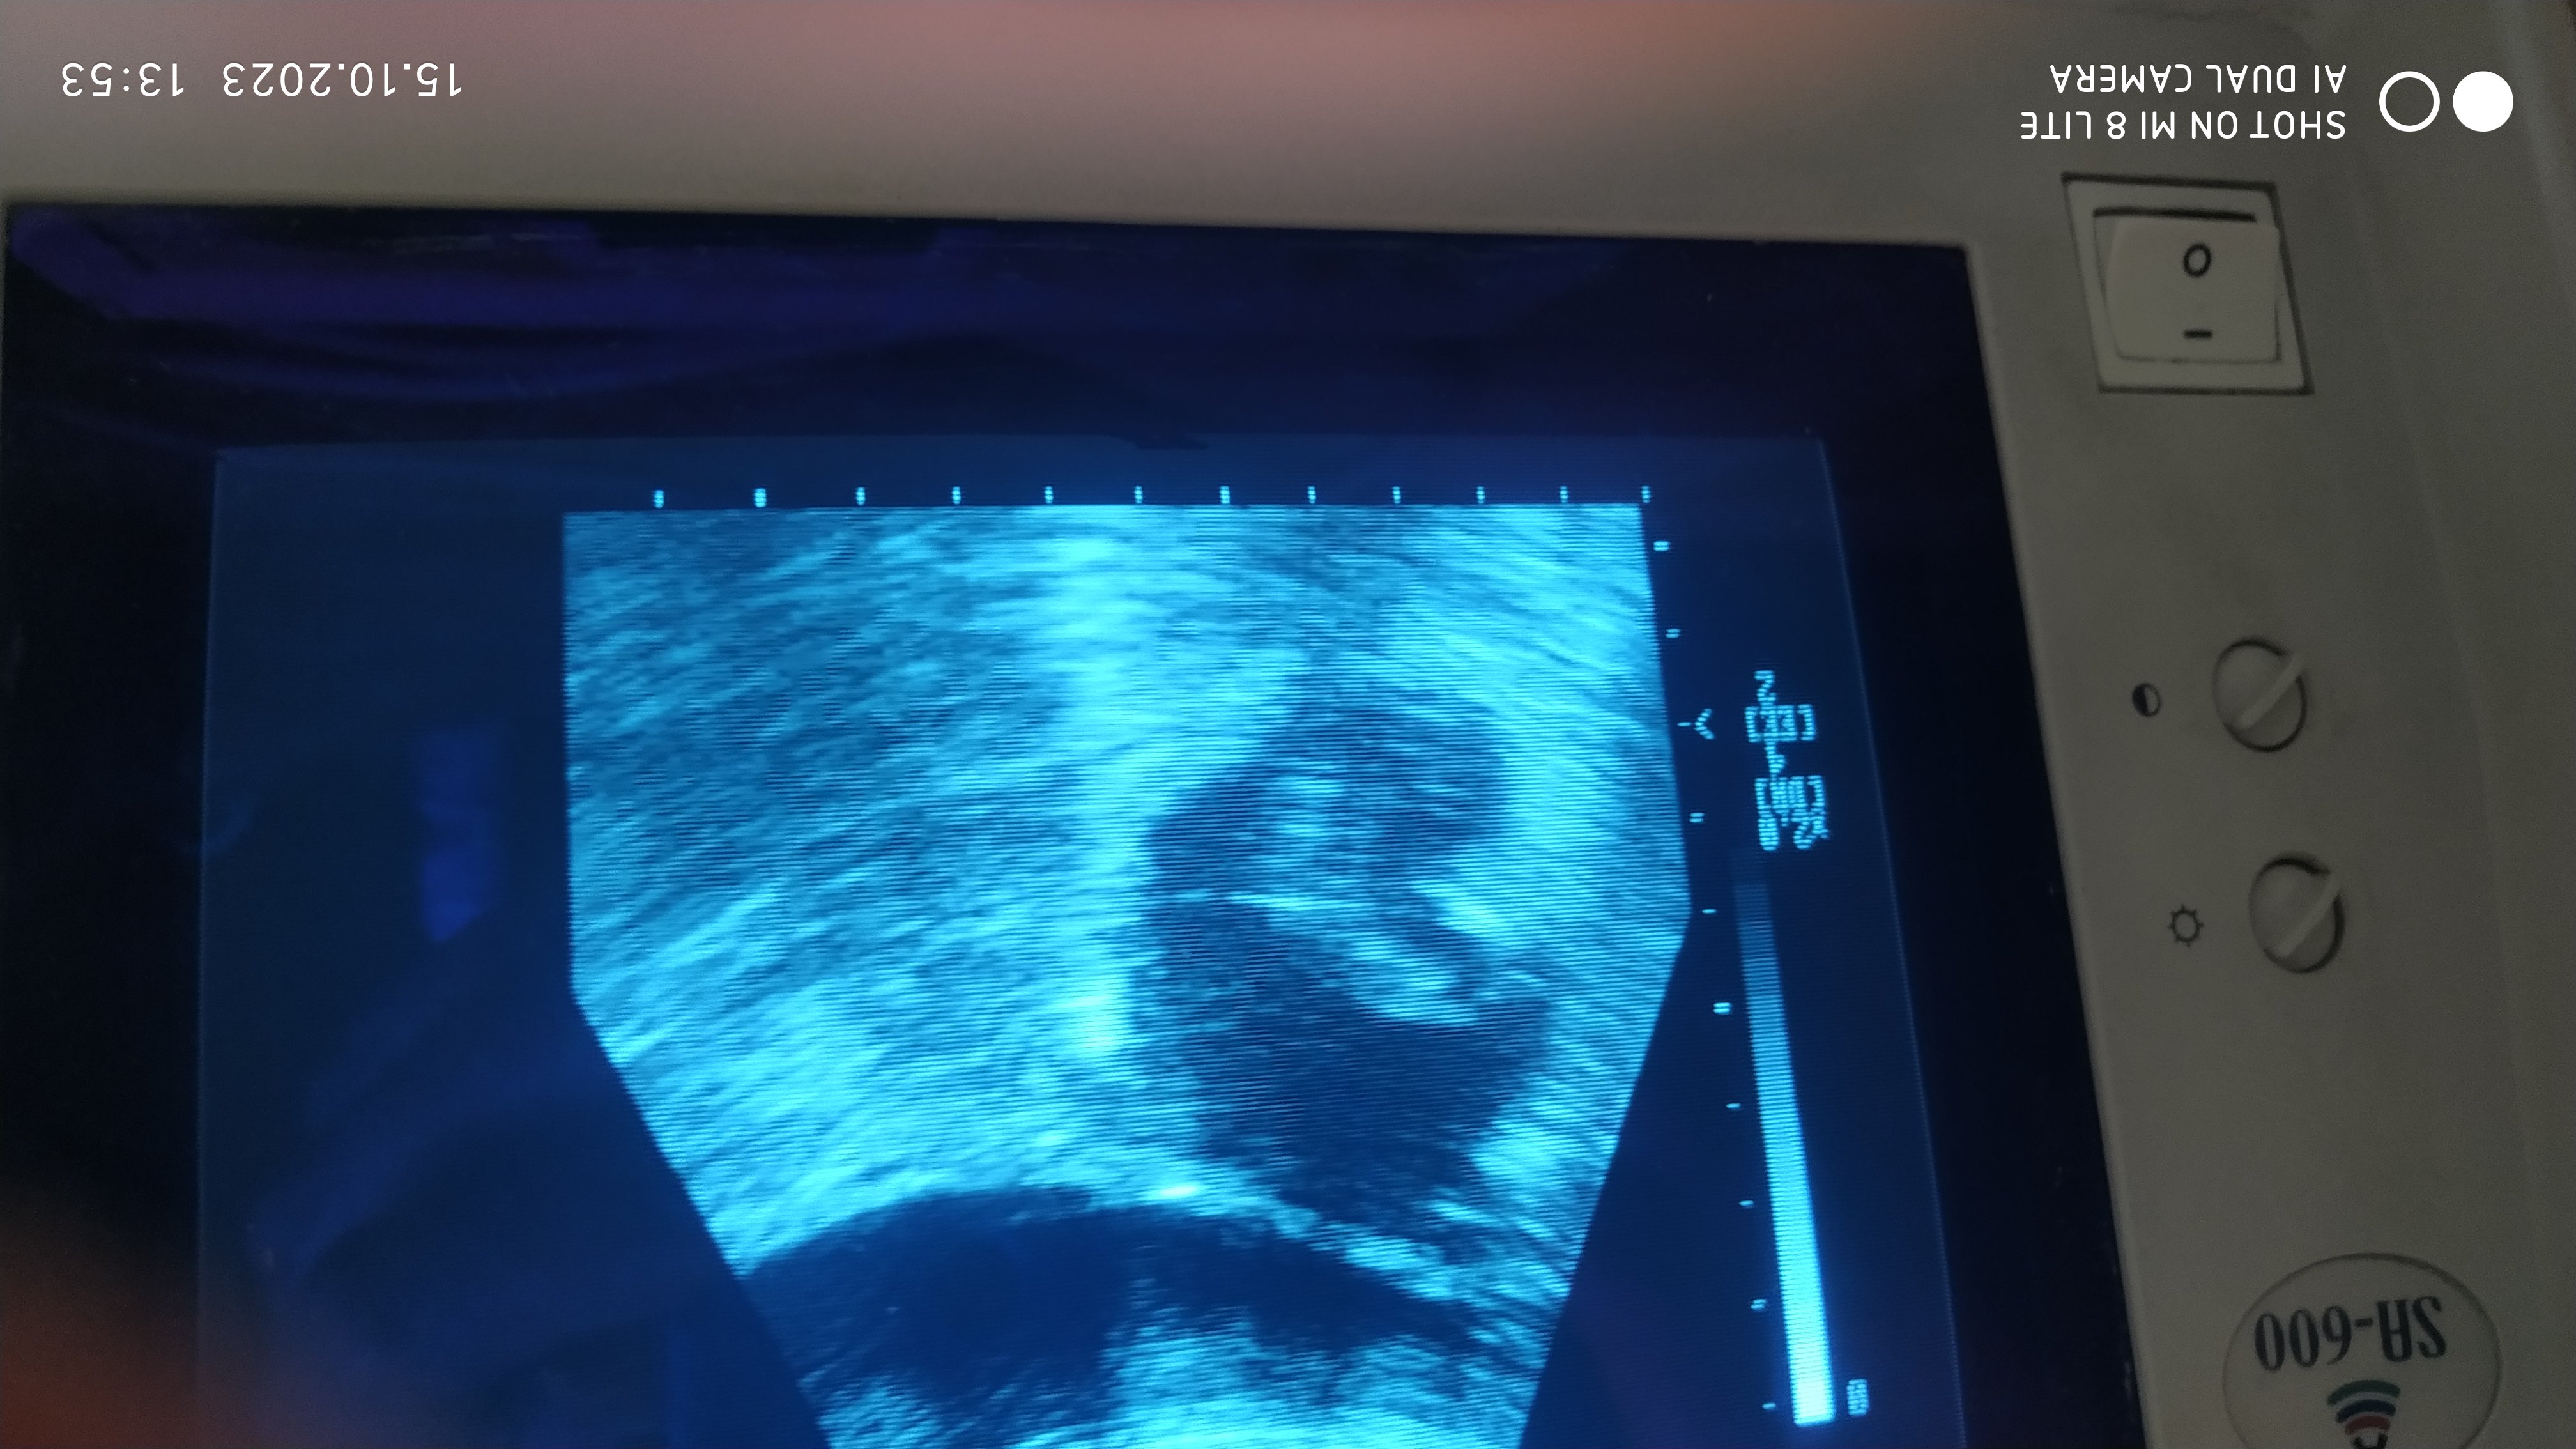

W oczekiwaniu na narodziny, przeprowadziliśmy badanie USG suki JAVY, która była kryta kilka tygodni po kryciu Rimy. Poniżej wynik badania.

Około 35 – 36 dzień ciąży.

Około 35 – 36 dzień ciąży.